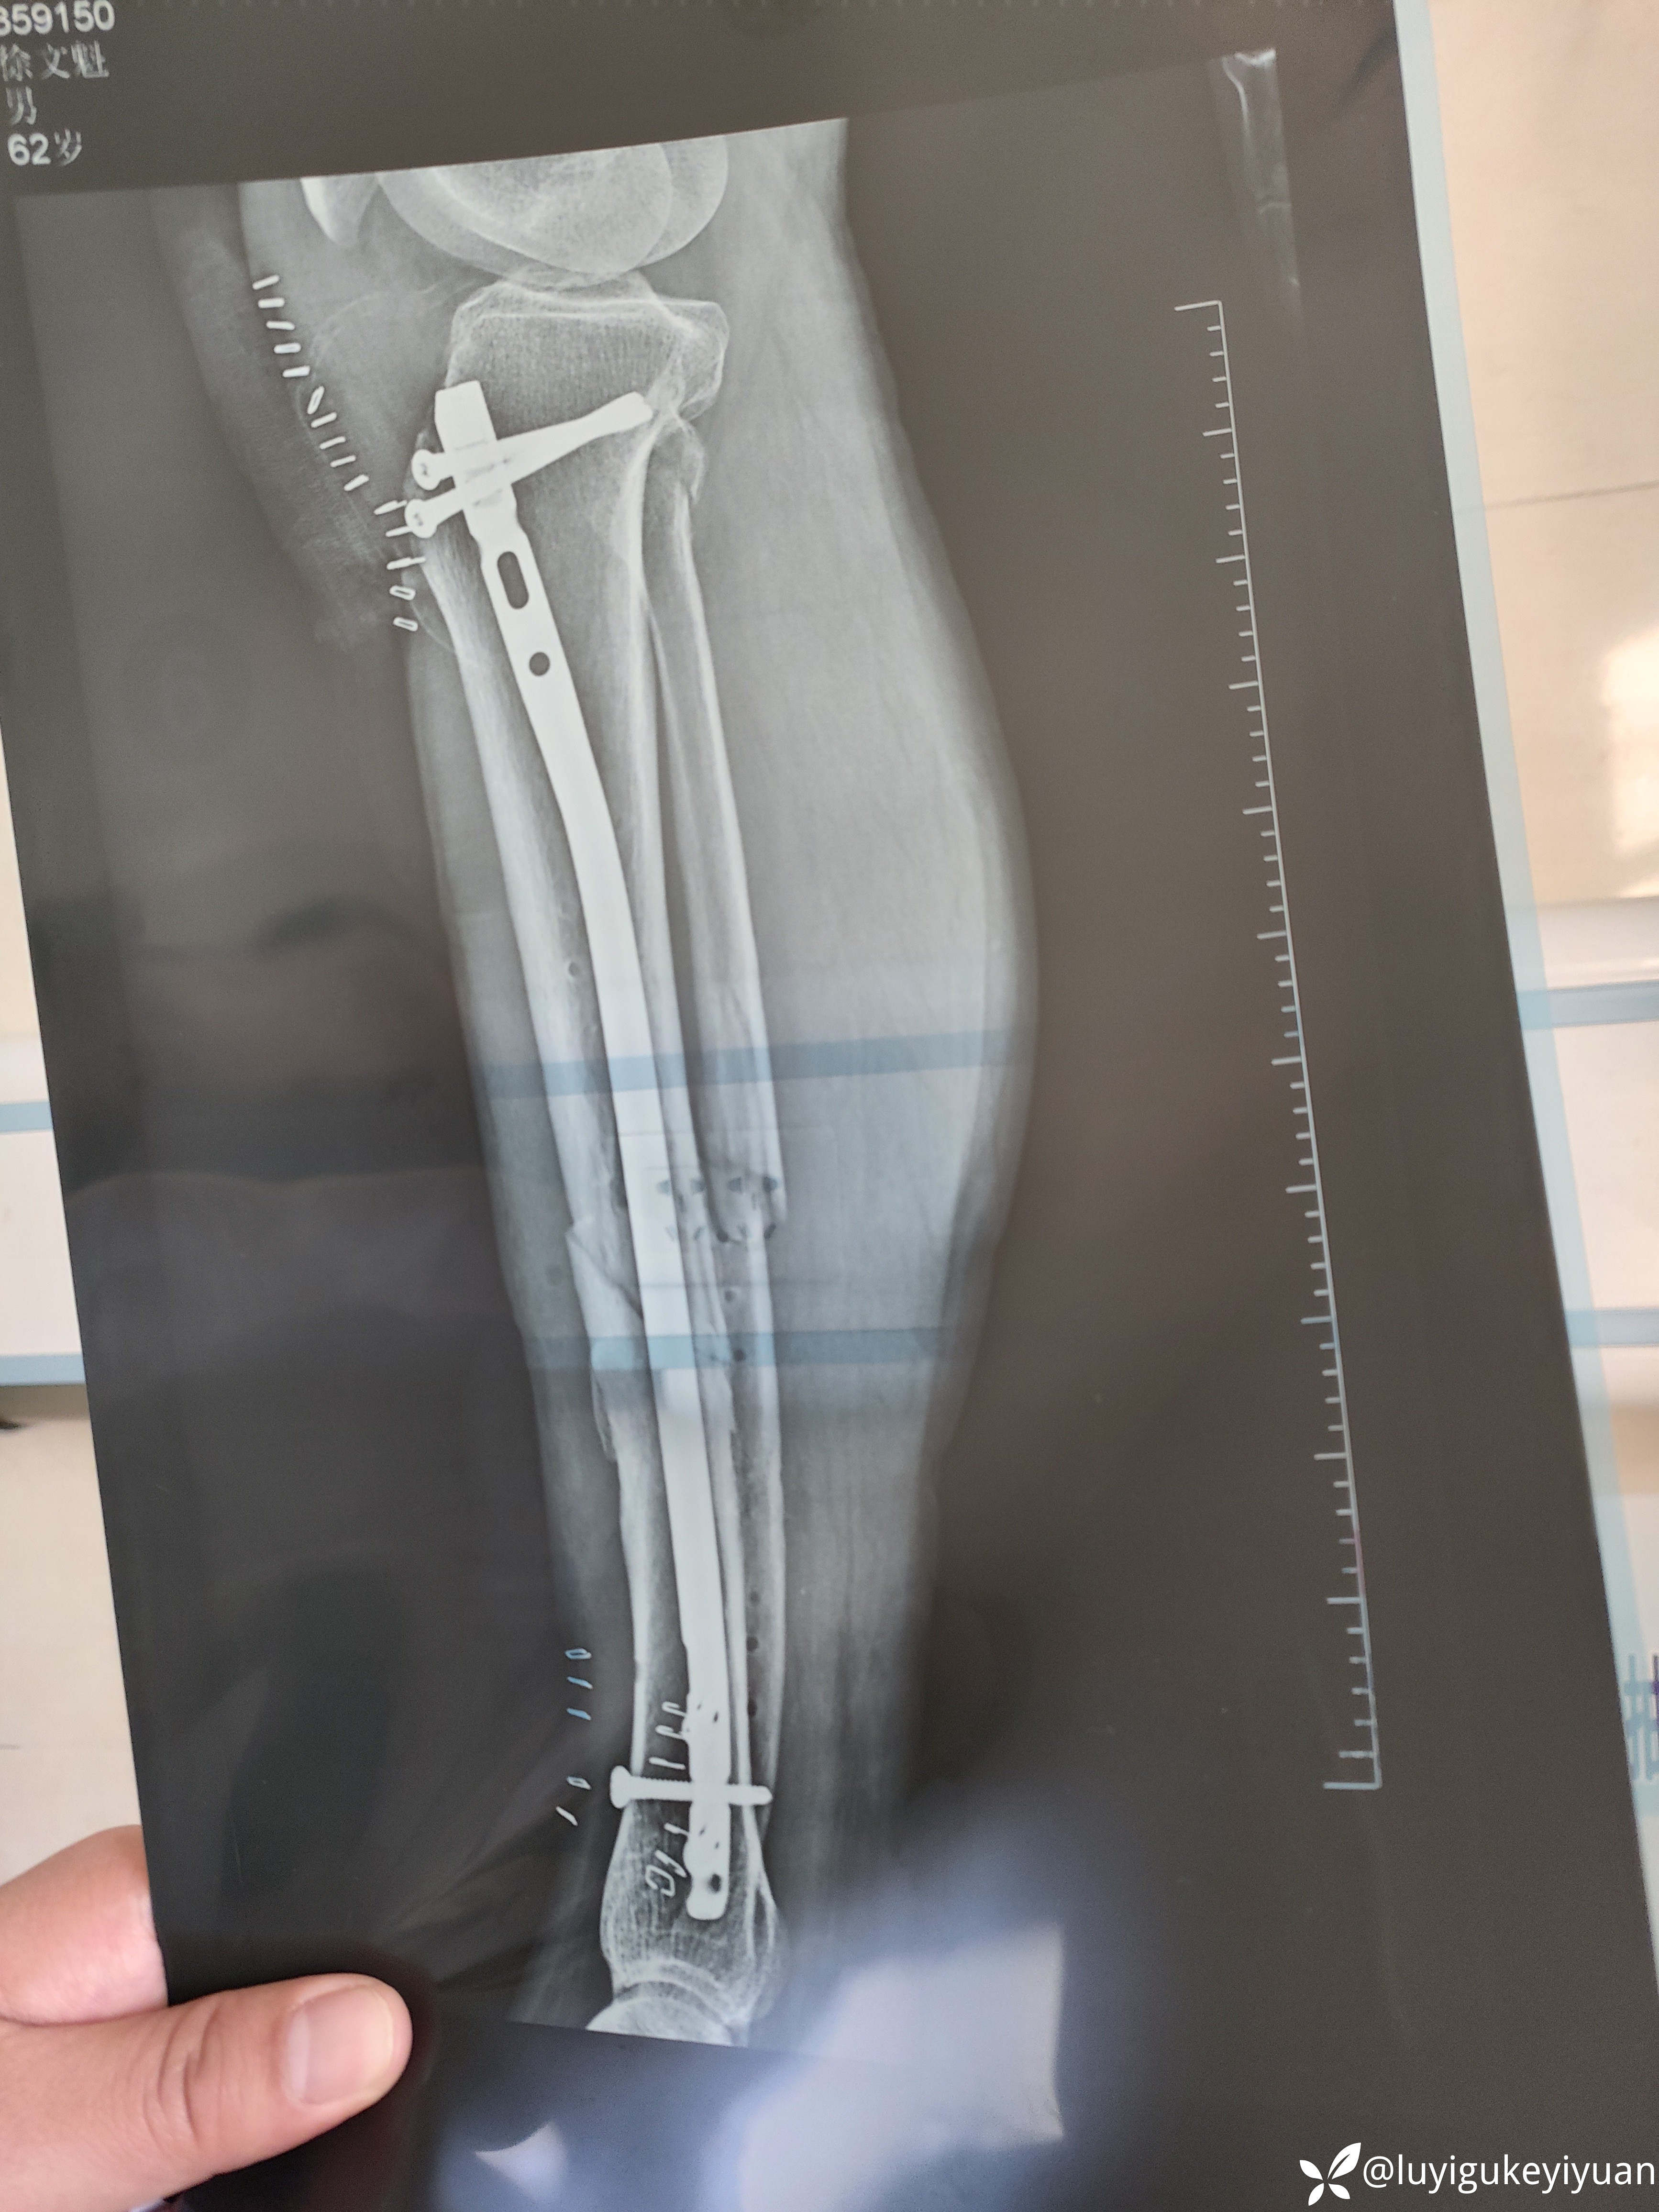

病例胫腓骨二次骨折

医患关系太紧张啊,术前谈话说的好好的,术后骨折部位不一定解剖复位,术后患者家属说手术不成功,真

无语!